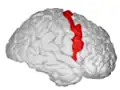

Precentral gyrus

The precentral gyrus is a prominent gyrus on the surface of the posterior frontal lobe of the brain. It is the site of the primary motor cortex that in humans is cytoarchitecturally defined as Brodmann area 4.

The precentral gyrus lies in front of the postcentral gyrus - mostly on the lateral (convex) side of each cerebral hemisphere - from which it is separated by the central sulcus. Its anterior border is represented by the precentral sulcus, while inferiorly it borders to the lateral sulcus (Sylvian fissure). Medially, it is contiguous with the paracentral lobule.

There is a precise somatotopic representation of the different body parts in the primary motor cortex, with the leg area located medially (close to the midline), and the head and face area located laterally on the convex side of the cerebral hemisphere (cortical homunculus). The arm and hand motor area is the largest and occupies the part of precentral gyrus, located inbetween the leg and face area.